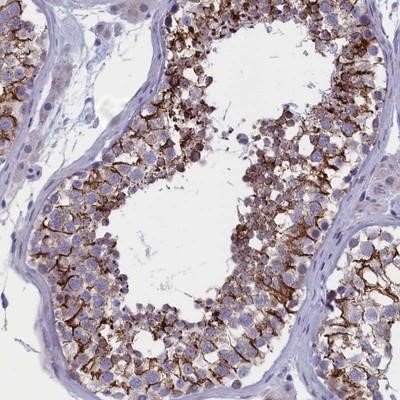

- Main image

- Experimental details

- Immunohistochemistry-Paraffin: BCNP Antibody [NBP1-90771] - Staining of human testis shows strong cytoplasmic and membranous positivity in cells in seminiferus ducts.